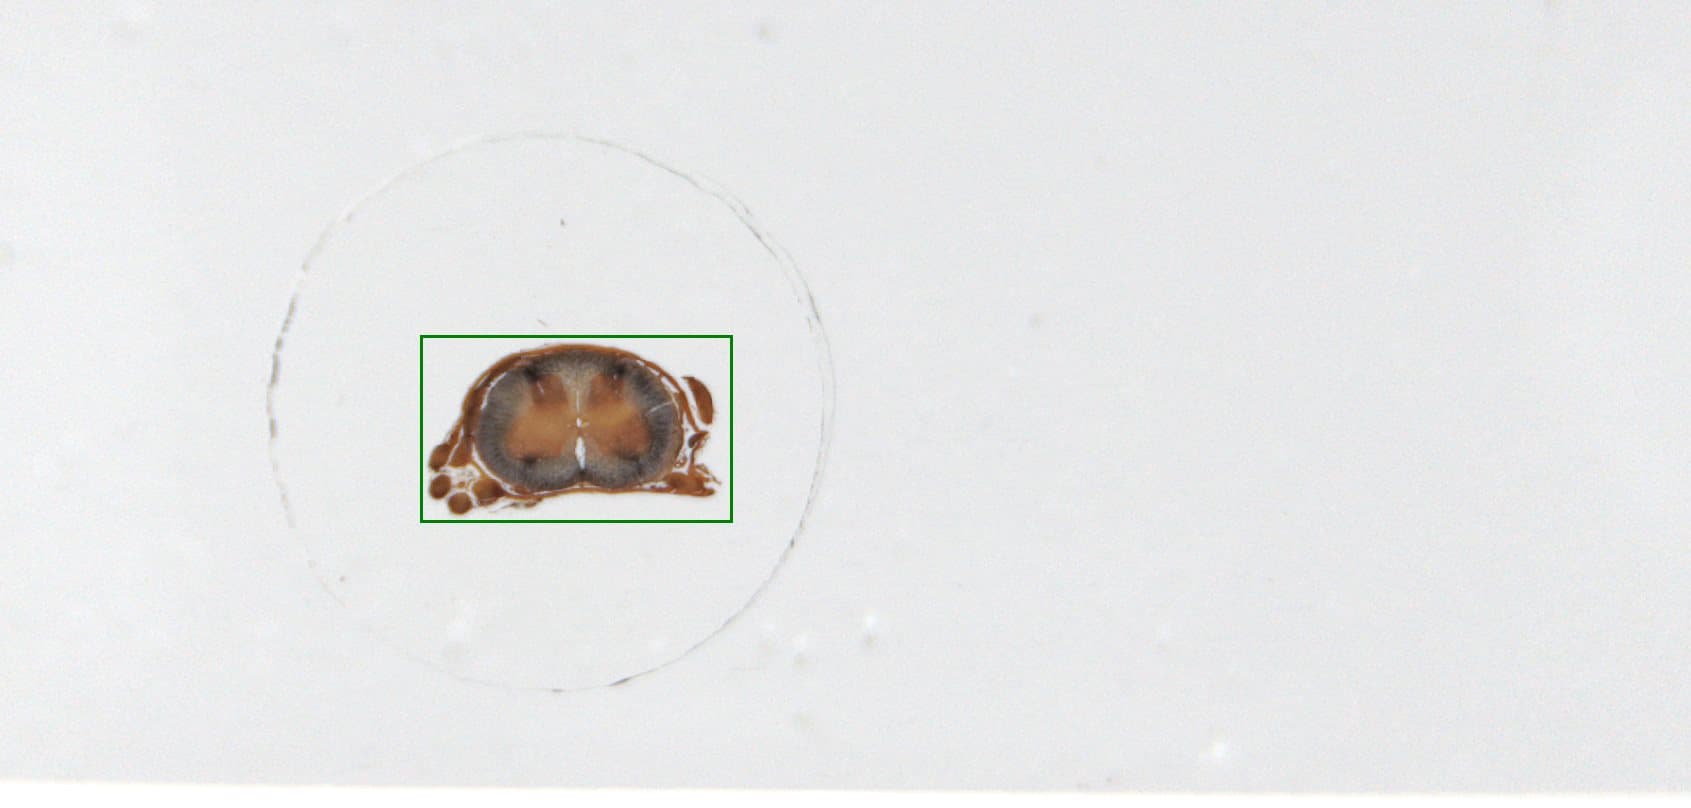

Spinal Cord

Scanned by uScopeHXII-20

Objective: 20x (0.65NA)

Fields: 323 (17×19) HD

36.956mm² (7.878mm × 4.691mm)

SpinalCord-HX20-HDX

Scan Date

13-Oct-2017 14:54

20x (0.65NA)

0.258µm/pixel

323 (17 × 19)